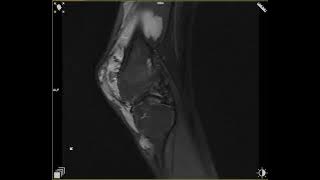

Video 1: achiziție PD cu saturația grăsimii la nivelul genunchiului; se pun în evidență structurile venoase de calibru crescut cu modificări secundare de osteocondrită.

Discuţie caz nr 51: sindromul Klippel-Trenaunay este o boală congenitală caracterizată prin triada: malformatii venoase, malformații cutanate capilare și creștere localizată a unei extremități. Este considerat un sindrom osteo-hipertrofic. Se poate datora persistenței venelor embrionice dintre care venă marginală laterală (venă Sevelle) este frecvent prezentă (la 68-80% din pacienți). Achizițiile T2 pun în evidența leziunile vasculare venoase și limfatice ca arii de hiperintensitate, iar imaginile RM evidențiază extensia malformațiilor vasculare cu flux redus la nivelul compartimentelor musculare precum și la nivel pelvin și rapoartele cu structurile adiacente precum și hipertrofie de țesut osos sau țesut moale.